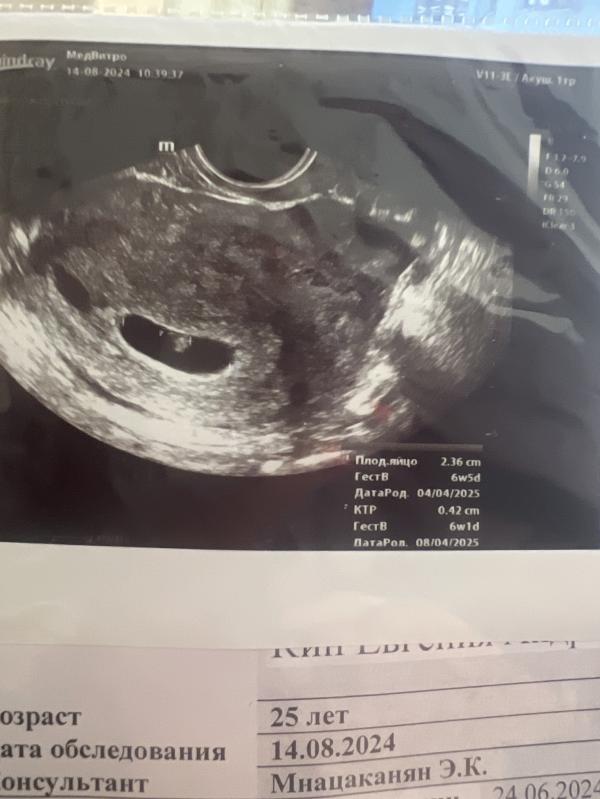

Вчера сходила на узи, беременность 6 недель, почти все хорошо. Повышен тонус матки и еще есть гематома. Теперь переживаю, может вызвать скорую и лечь на сохранение

Я вчера была на узи, срок 5 недель поставили . Нашли гематому и повышаем тонус матки. Назначили дюфастон и постельный режим , свечи с папаверином на ночь. У вас есть мазня ?

Я по снимку сразу поняла, что гематома. У меня черный пояс уже)))

Я наблюдала, часто делала узи, (у меня нашли на 6, к 8 недели она выросла до 15 на 3 мм), прописали утрожестан. На скрининге в 11 недель ничего не нашли